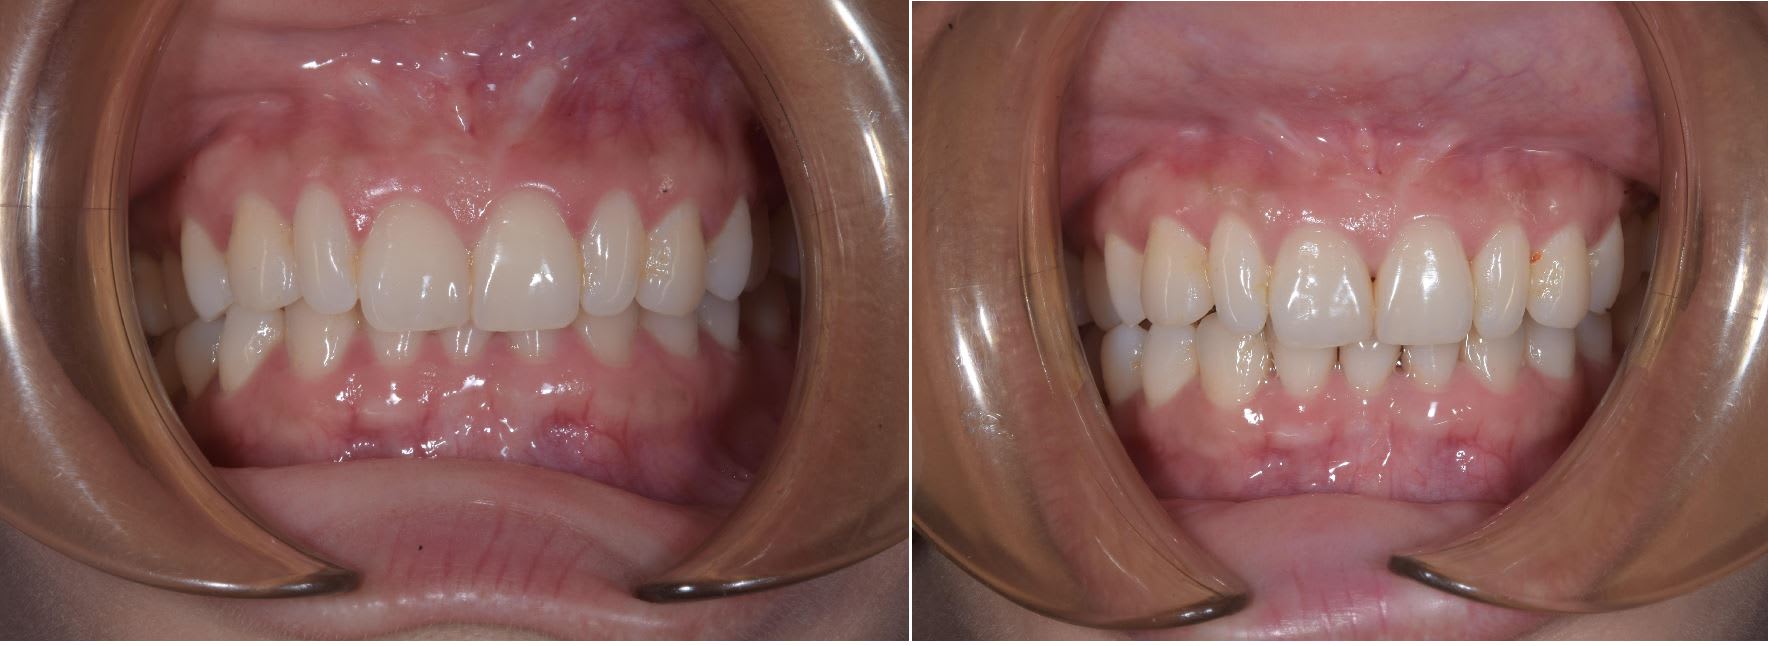

Et le résultat après trois mois.

Très content hier car j'ai envoyé les même photo au Pr Hee Moon Kyung avec qui j'avait eu auparvant des discussion sur les moyens possible pour torquer des dent avec les 2D. Un ortho Coréen fait ça avec une combinaison de 2D et d'aligner . Il m'a félicité pour cette technique.

Le truc marrant c'est que c'est lui qui m'avait donné l'idée quand j'était en master. Son livre décrit l'utilisation de bracket double slot horizontal et un slot vertical. Le slot vertical étant utilisé pour tipper la dent en mésial ou distal avec l'utilisation de ressort. Je me disait que si l'on pouvait avoir l'équivalent pour le torque cela saurait bien pratique :-)

A ma connaissance je suis le premier à avoir procédé de la sorte, au moins avec des 2D.